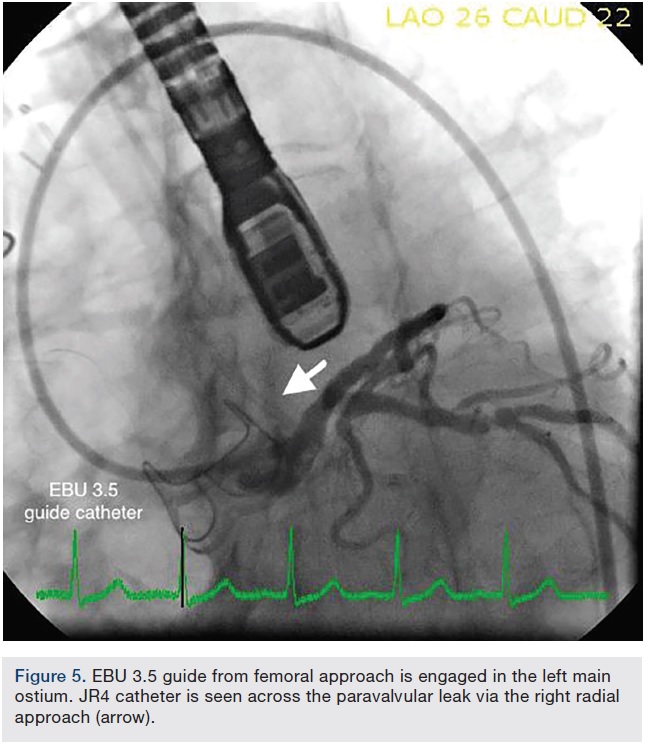

The paravalvular regurgitation began near the left main coronary ostium and extended anteriorly, measuring approximately 1.25cm long and .67cm wide (Figure 3A-B). Both right femoral and right radial accesses were obtained using a 6 French sheath. The aortography, performed via a right radial approach, also demonstrated the paravalvular leak (Figure 4). After crossing the PVL with a .035-inch Glidewire (Terumo Interventional Systems), the guide catheter was unable to advance through the PVL over the .035-inch Glidewire, despite multiple attempts via the femoral approach with different catheters. Attempts were made using a 6 French multipurpose guide catheter, a 5 French Judkins right (JR)4 guide catheter, a mother-daughter technique with a multipurpose guide and a diagnostic catheter, a 6 French, 90cm Destination sheath (Terumo), and a 5 French, 90cm Ansel sheath (Cook Medical).

At this point, the approach was changed. The Extra Back-Up (EBU) 3.5 guide was advanced from the femoral approach to selectively engage the left main ostium. The EBU guide was left in place to protect the left main ostia, because the paravalvular leak was closed to the left main origin. Using a 5 French JR4 guide catheter via the right radial access, we were able to successfully advance the JR4 guide catheter through the paravalvular leak (Figure 5). A 5 French, 90cm Destination sheath was telescoped over the 5 French guide catheter across the PVL. Under TEE and fluoroscopic guidance, an 8mm Amplatzer Vascular Plug (St. Jude Medical) was deployed across the PVL and through the Destination sheath, and a tug test was performed. (Figure 6A-B, 7). The final TEE imaging showed a well-deployed Amplatzer Vascular Plug into the paravalvular aortic annular defect, with a significant decrease in paravalvular regurgitation compared with the pre-procedure study (Figures 8, 9). A trace to mild paravalvular insufficiency and a mild intrinsic central aortic insufficiency were seen (Figure 10). A hemostatic band and a vascular closure device were used to achieve hemostasis in the radial artery and femoral artery, respectively. The patient tolerated the procedure well and she was discharged from the hospital the next morning. At her follow-up visit, she had significant improvement in her symptoms.